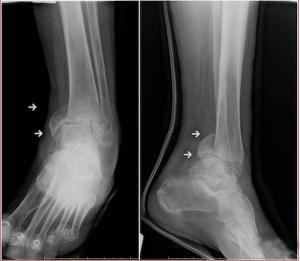

(图:入院时,张先生所照射的X光图,踝关节肿胀)

检查显示:踝关节畸形明显狭窄,肿胀压痛,脚踝关节活动受限,关节间隙尚可见,骨质疏松明显,并有演变为晚期的趋势。